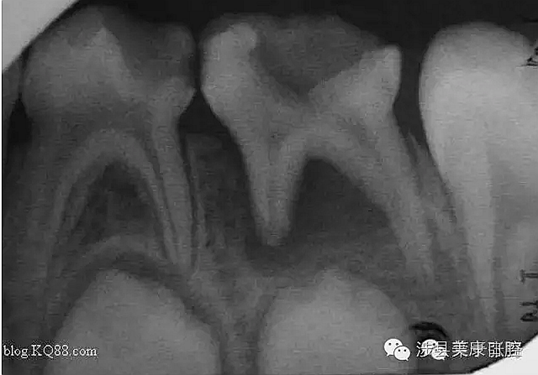

普通家長看了這張牙片估計(jì)能看出來孩子的牙不好,但是究竟不好到什么程度呢,讓葉子姐告訴大家:

上圖孩子的乳牙感染已經(jīng)將下面骨感染到吸收消失,并且直接影響到了下面的恒牙胚,家長們上點(diǎn)心吧。那些說乳牙不用治療,換牙就會好的人(包括醫(yī)生)還是睜開眼睛看看吧,不要自欺欺人,更不要用自己的錯誤誤導(dǎo)他人誤導(dǎo)大眾。

網(wǎng)友又不明白了,什么叫吸收消失?看x片看不懂哎......

黑色部分表示那里的骨頭感染已經(jīng)爛沒有了,消失了,牙胚應(yīng)該在健康頜骨里孕育生長發(fā)育,現(xiàn)在在感染的病灶里生長,在膿水里侵泡。

又有好奇網(wǎng)友問他怎么有那么多牙?

乳牙下面有恒牙孕育著。